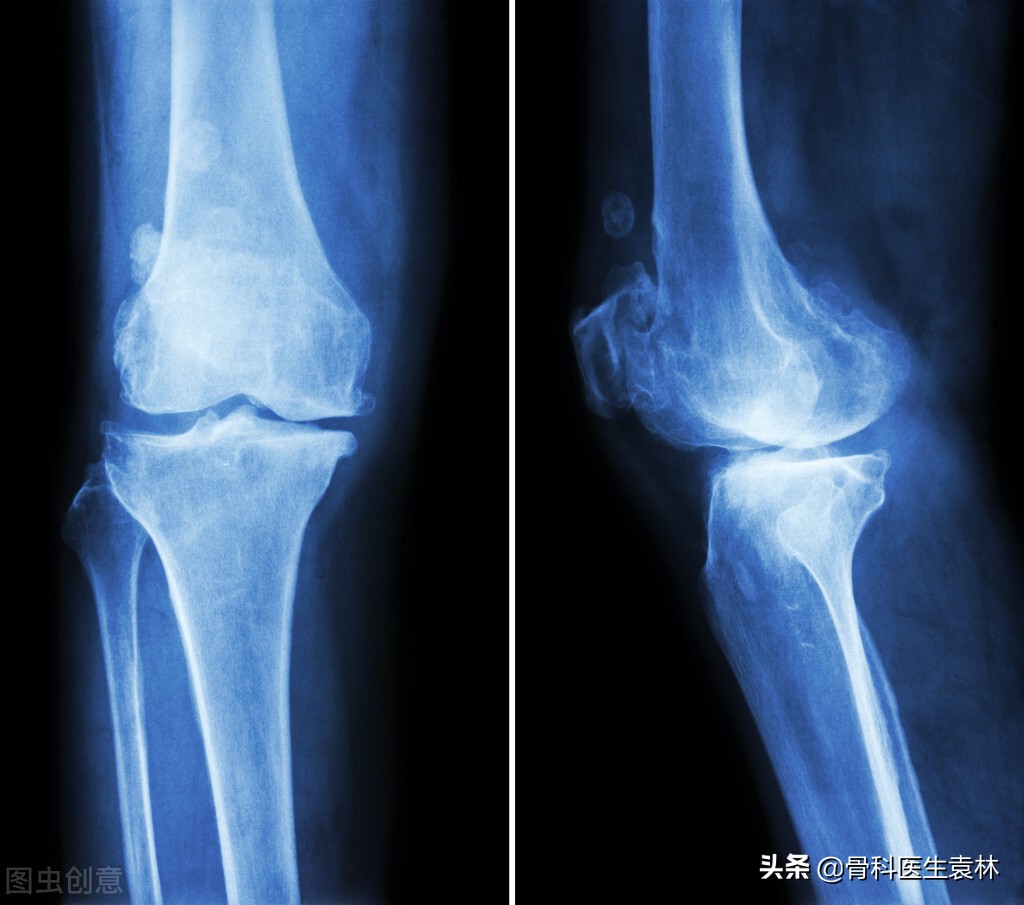

对骨刺不必恐惧。骨刺并非长入骨内的刺,在侧位X线片上是“刺”状,而在正位X线片上一般不显示。因为它有一种自身保护作用,以一般不会疼痛。有些患者出现疼痛,是因为有软策划(韧带、筋膜)损伤或劳损;有的是由于骨骼、软策划退行性病变产生导致疼痛的介质;有的是由于以上原因引起的骨内压增高。在休息时仍然疼痛(医学上称为休息痛),但不是刀割样锐性痛,而是沉闷、钝痛、酸困和说不出